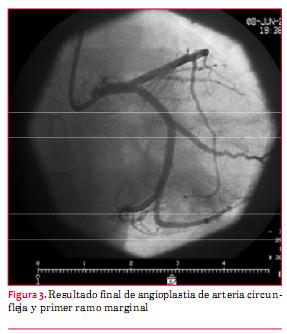

Se realiza angioplastia de arteria circunfleja y primer ramo marginal con stent Promus Premier 3,5 por 28 mm y stent Promus Premier 2,5 por16 mm, respectivamente, con buen resultado angiográfico (figura 3), alivio del dolor y normalización del ECG (figura 4).